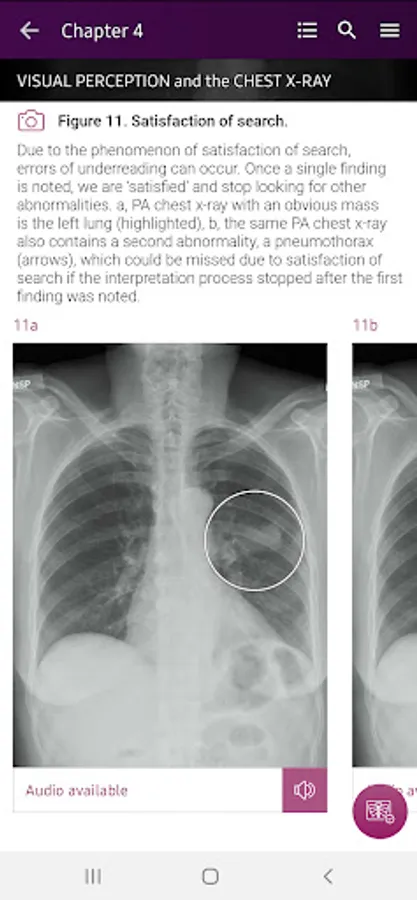

• Help you develop the skill of identifying all chest x-ray pathologies, not only the obvious.